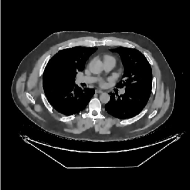

This paper was inspired by a simple observation related to our recent study [34]: for the penalized weighted-least squares (PWLS) reconstruction method using prior with a learned ST (PWLS-ST-) [34], the sparsification error histograms match a Laplace distribution over the iterations; see Fig. 1. The question then arises, “Does the learned prior experience model mismatch in testing stage?” To answer this question, we aim to investigate learned STs for regularization. This paper

The term denotes a -based sparsification error [3, 4, 5]. We expect to be more robust to sparsity model mismatch than the -based sparsification error used in [34, 36]. Fig. 1 shows histograms of sparsification error at different outer iterations of the PWLS-ST- method. Over the iterations, the sparsification error histograms appear more like a Laplace distribution than a Gaussian distribution. This observation suggests that the proposed prior model is more suitable than the prior model for PWLS-ST-based reconstruction. Section III-B1 shows that the proposed -based sparsification error term, , improves the accuracy of reconstruction compared to the prior model in [34, 36].

| views | ||||

| (a) , | (b) , | (c) , | (d) , |